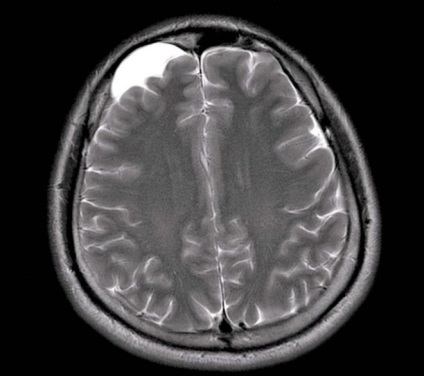

Cele mai multe tumori de acest tip, în cazul în care acestea sunt boli congenitale și creșterea în dimensiune pe o perioadă lungă de timp, medicii recomandă să nu pentru a elimina chirurgical, dar planificat să-și petreacă cursul conservator de tratament și pentru a monitoriza dimensiunea chistului arahnoidici a lobului temporal stâng. controlul tumorii profilactică în acest caz, se produce anual folosind RMN sau CT-scan a zonelor cu probleme și țesuturile înconjurătoare.